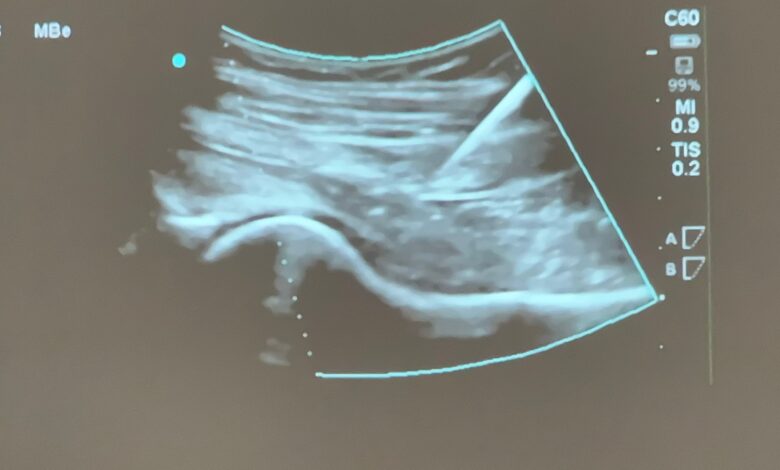

Si tratta dell’infiltrazione ecoguidata dell’anca, una procedura terapeutica che offre un sollievo efficace ai pazienti che non rispondono alla terapia farmacologica o ai percorsi fisioterapici.

La prestazione è ora disponibile in convenzione sia presso la Radiologia sia presso il Servizio di Terapia del dolore della ASL di Pescara. L’impiego della guida ecografica consente un’esecuzione precisa e sicura dell’infiltrazione, riducendo sensibilmente il rischio di complicanze infettive o vascolo-nervose.